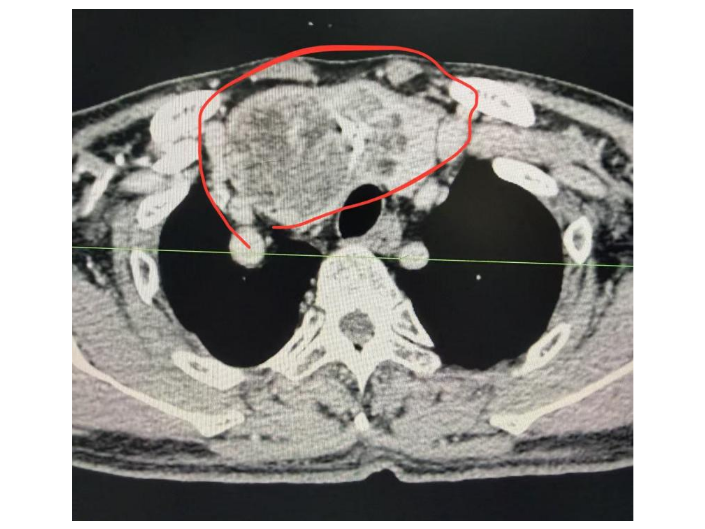

红网时刻新闻4月13日讯(通讯员 王环)近日,62岁患者邹某某因严重呼吸困难,慕名来到衡阳市中心医院乳甲外科,找到科室主任罗琼博士求诊。经CT检查发现,邹某某患有胸骨后巨大甲状腺肿,气管被严重挤压偏移,最窄处仅剩正常管径的三分之一,手术风险极高。